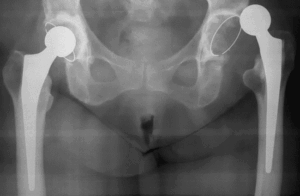

Вывих эндопротеза тазобедренного сустава

Вывих эндопротеза тазобедренного сустава Вывих бедра — редкая и неприятная патология, возникающая по разным причинам. Лечение в этом случае может быть консервативным или хирургическим. Все зависит от характера вывиха и самочувствия пациента. Вывих эндопротеза: причины По статистике вывих эндопротеза чаще диагностируется у представителей женского пола, чем у представителей мужского пола. В группу риска также входят …